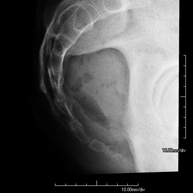

- X-ray arthrography

This X-ray based procedure involves injecting a contrast agent into the joint to detect lesions in certain structures (cartilage, bone, tendons, etc.) by observing the distribution of the contrast agent.